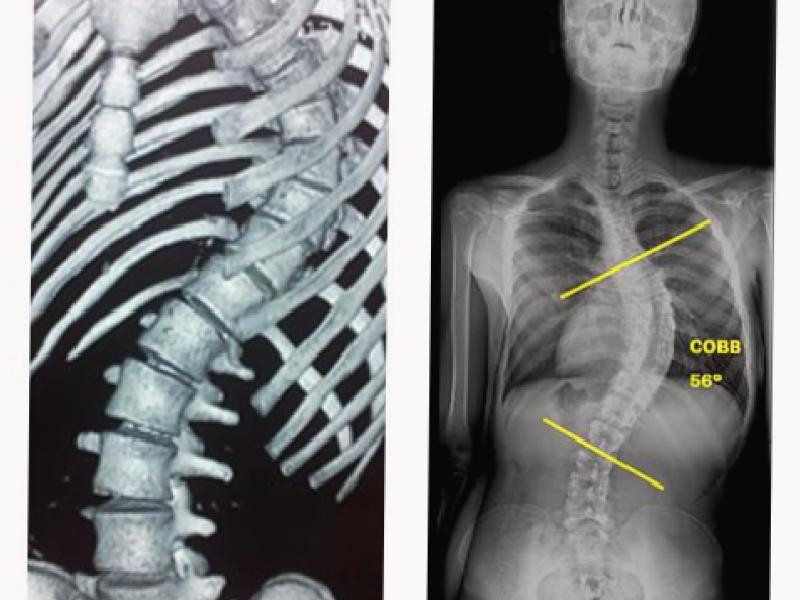

Figure 1. 3D computed tomography image of the patient with idiopathic scoliosis.

Figure 2. Measurement of the scoliosis angle in the anterior-posterior radiograph of the patient with idiopathic scoliosis